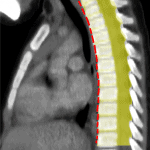

U trung thất sau (Posterior Mediastinal Tumor) chiếm 20-30% bệnh lý trung thất, chủ yếu là các u có nguồn gốc thần kinh và sụn. U trung thất sau có thể là những khối u nguyên phát hoặc thứ phát, lành tính hoặc ác tính. Ở người lớn u lành tính chiếm 15%, ở trẻ em < 16 tuổi u ác tính chiếm 60%. U trung thất sau thường phát triển chậm và tiềm tàng trong một thời gian dài. Đa phần được phát hiện tình cờ. Khi khối u phát triển mạnh gây chèn ép hoặc xâm lấn có thể xuất hiện các triệu chứng: đau ngực, ho, khó thở, khó nuốt...